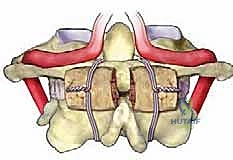

التشريح المعقد للفقرات العنقية C1-C2: تحدي الجراحين الأول

الفقرة العنقية الأولى (C1) - الأطلس (Atlas)

سُميت هذه الفقرة بـ "الأطلس" تيمناً بالإله اليوناني الذي يحمل قبة السماء على كتفيه، لأن هذه الفقرة تحمل جمجمة الإنسان. إنها فقرة فريدة جداً؛ فهي تفتقر تماماً إلى "جسم فقري" (Vertebral Body) وإلى "نتوء شوكي" (Spinous Process) بارز للخلف، وهما المكونان الأساسيان لأي فقرة أخرى.

بدلاً من ذلك، تتكون C1 من حلقة عظمية متينة تتألف من:

1. قوس أمامي (Anterior Arch): صغير نسبياً.

2. قوس خلفي (Posterior Arch): أطول ويشكل الجزء الخلفي من الحلقة.

3. كتلتين مفصليتين جانبيتين (Lateral Masses): وهما الدعامتان القويتان اللتان تحملان وزن الجمجمة وتنقلانه إلى الفقرات السفلية.

الخطر التشريحي (الشريان الفقري): على السطح العلوي للقوس الخلفي للفقرة C1، يوجد أخدود بالغ الأهمية يمر فيه الشريان الفقري (Vertebral Artery)، وهو الشريان الرئيسي الذي يغذي الدماغ بالدم. في بعض البشر، يكون هذا الأخدود مغطى بجسر عظمي خلقي يُسمى (Ponticulus Posticus). يجب على الجراح الخبير مثل الدكتور هطيف تحديد هذا الشريان بدقة متناهية وحمايته أثناء وضع المسامير، لأن أي إصابة له قد تؤدي إلى سكتة دماغية كارثية.

الفقرة العنقية الثانية (C2) - المحور (Axis)

تُعد الفقرة C2، أو المحور، أقوى فقرات العمود الفقري العنقي. الميزة الأبرز والأكثر أهمية في هذه الفقرة هي النتوء السني (Odontoid Process أو Dens).

هذا النتوء هو عبارة عن بروز عظمي يشبه الوتد يمتد للأعلى من جسم الفقرة C2 ليدخل داخل الحلقة العظمية للفقرة C1. يعمل هذا النتوء كمحور دوران تدور حوله الفقرة C1 (ومعها الجمجمة). يتم تثبيت هذا النتوء السني بقوة في مكانه ضد القوس الأمامي للفقرة C1 بواسطة "الرباط المستعرض" (Transverse Ligament) القوي جداً.

تتميز C2 أيضاً بصفائح عظمية (Laminae) سميكة جداً ونتوء شوكي كبير ومشقوق، مما يوفر نقاط ارتكاز ممتازة للعضلات وللأدوات الجراحية (المسامير) أثناء عملية التثبيت.